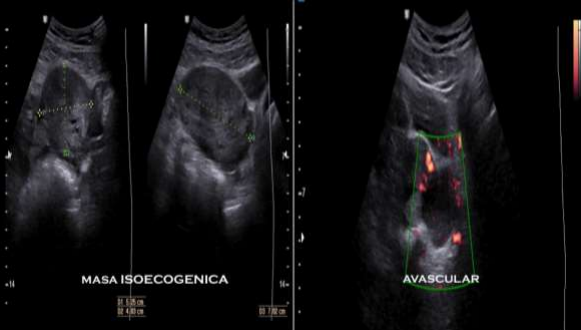

The gynecological pelvic ultrasound (fig. 1) as a diagnostic aid showed a uterus in AVF measuring 63*45*36 mm, with a mass of avascular isoechoic content measuring 53*48*76 mm compatible with ovarian torsion.

Figure 1. Ultrasound with evidence of an isoechogenic mass, with an enlarged, avascular ovary.